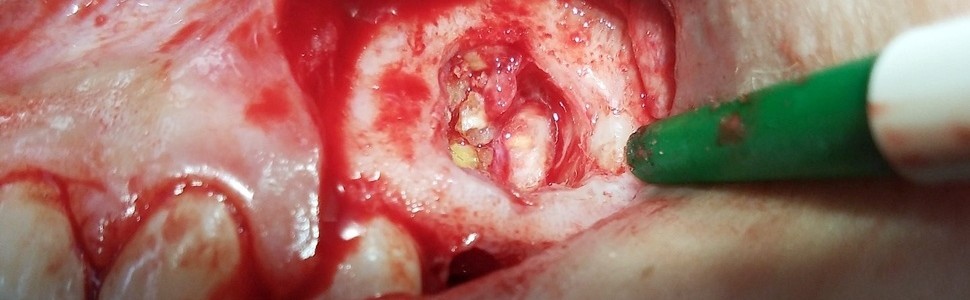

Odontoma belongs to tumors of jaws which are considered to be hamartomatous malformations. These tumors develop inside jaws and they may disorder tooth eruption or location of tooth bud.

The study shows a case of compound odontoma (odontoma, compound type – OCp) in a 14-year-old boy. The patient was sent for treatment by his general dentist and the tumor was found accidentally during routine OPG examination. The medical treatment contained surgical treatment, intra and postoperative course was successful.